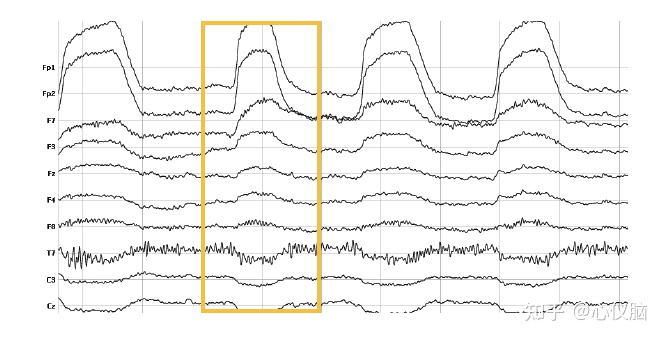

1.1眨眼(VGOD)

眨眼反应主要是由大小50-100μV、一般持续200-400ms的单相偏移组成。不过眨眼反应的最显著特征在于,眼睛上方和下方部位的电位极性相反。